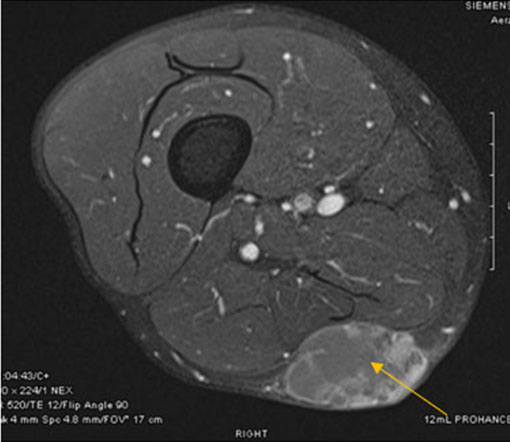

Three days after the onset of the strep pyogenes bacteremia, the patient experienced altered mental status and generalized seizure leading to pulseless electrical activity cardiac arrest. Return of spontaneous circulation was achieved following cardiopulmonary resuscitation. He remained unarousable following resuscitation. Neuroimaging revealed bilateral white matter edema in the posterior cerebral hemispheres; findings that are consistent with PRES and are depicted in Figure 2. Lumbar puncture was unremarkable without evidence of infectious process. Notable, he had no BK or JC virus reactivation. He remained hypertensive despite multiple anti-hypertensive agents and ultimately required maximal doses of a Nicardipine drip to achieve even moderate response. Electroencephalography demonstrated severe encephalopathy, but no seizure activity. Daily therapeutic plasma exchange was initiated and was given daily for three days followed by daily post-exchange Eculizumab. Remarkably, after 72 hours of therapy, he had complete neurologic recovery along with improvement in hemolysis indices. He received 10 total weeks of Eculizumab therapy.

Figure 2: Axial flair sequence of brain magnetic resonance imagining demonstrating bilateral white matter hyperintensities in the posterior region consistent with PRES.